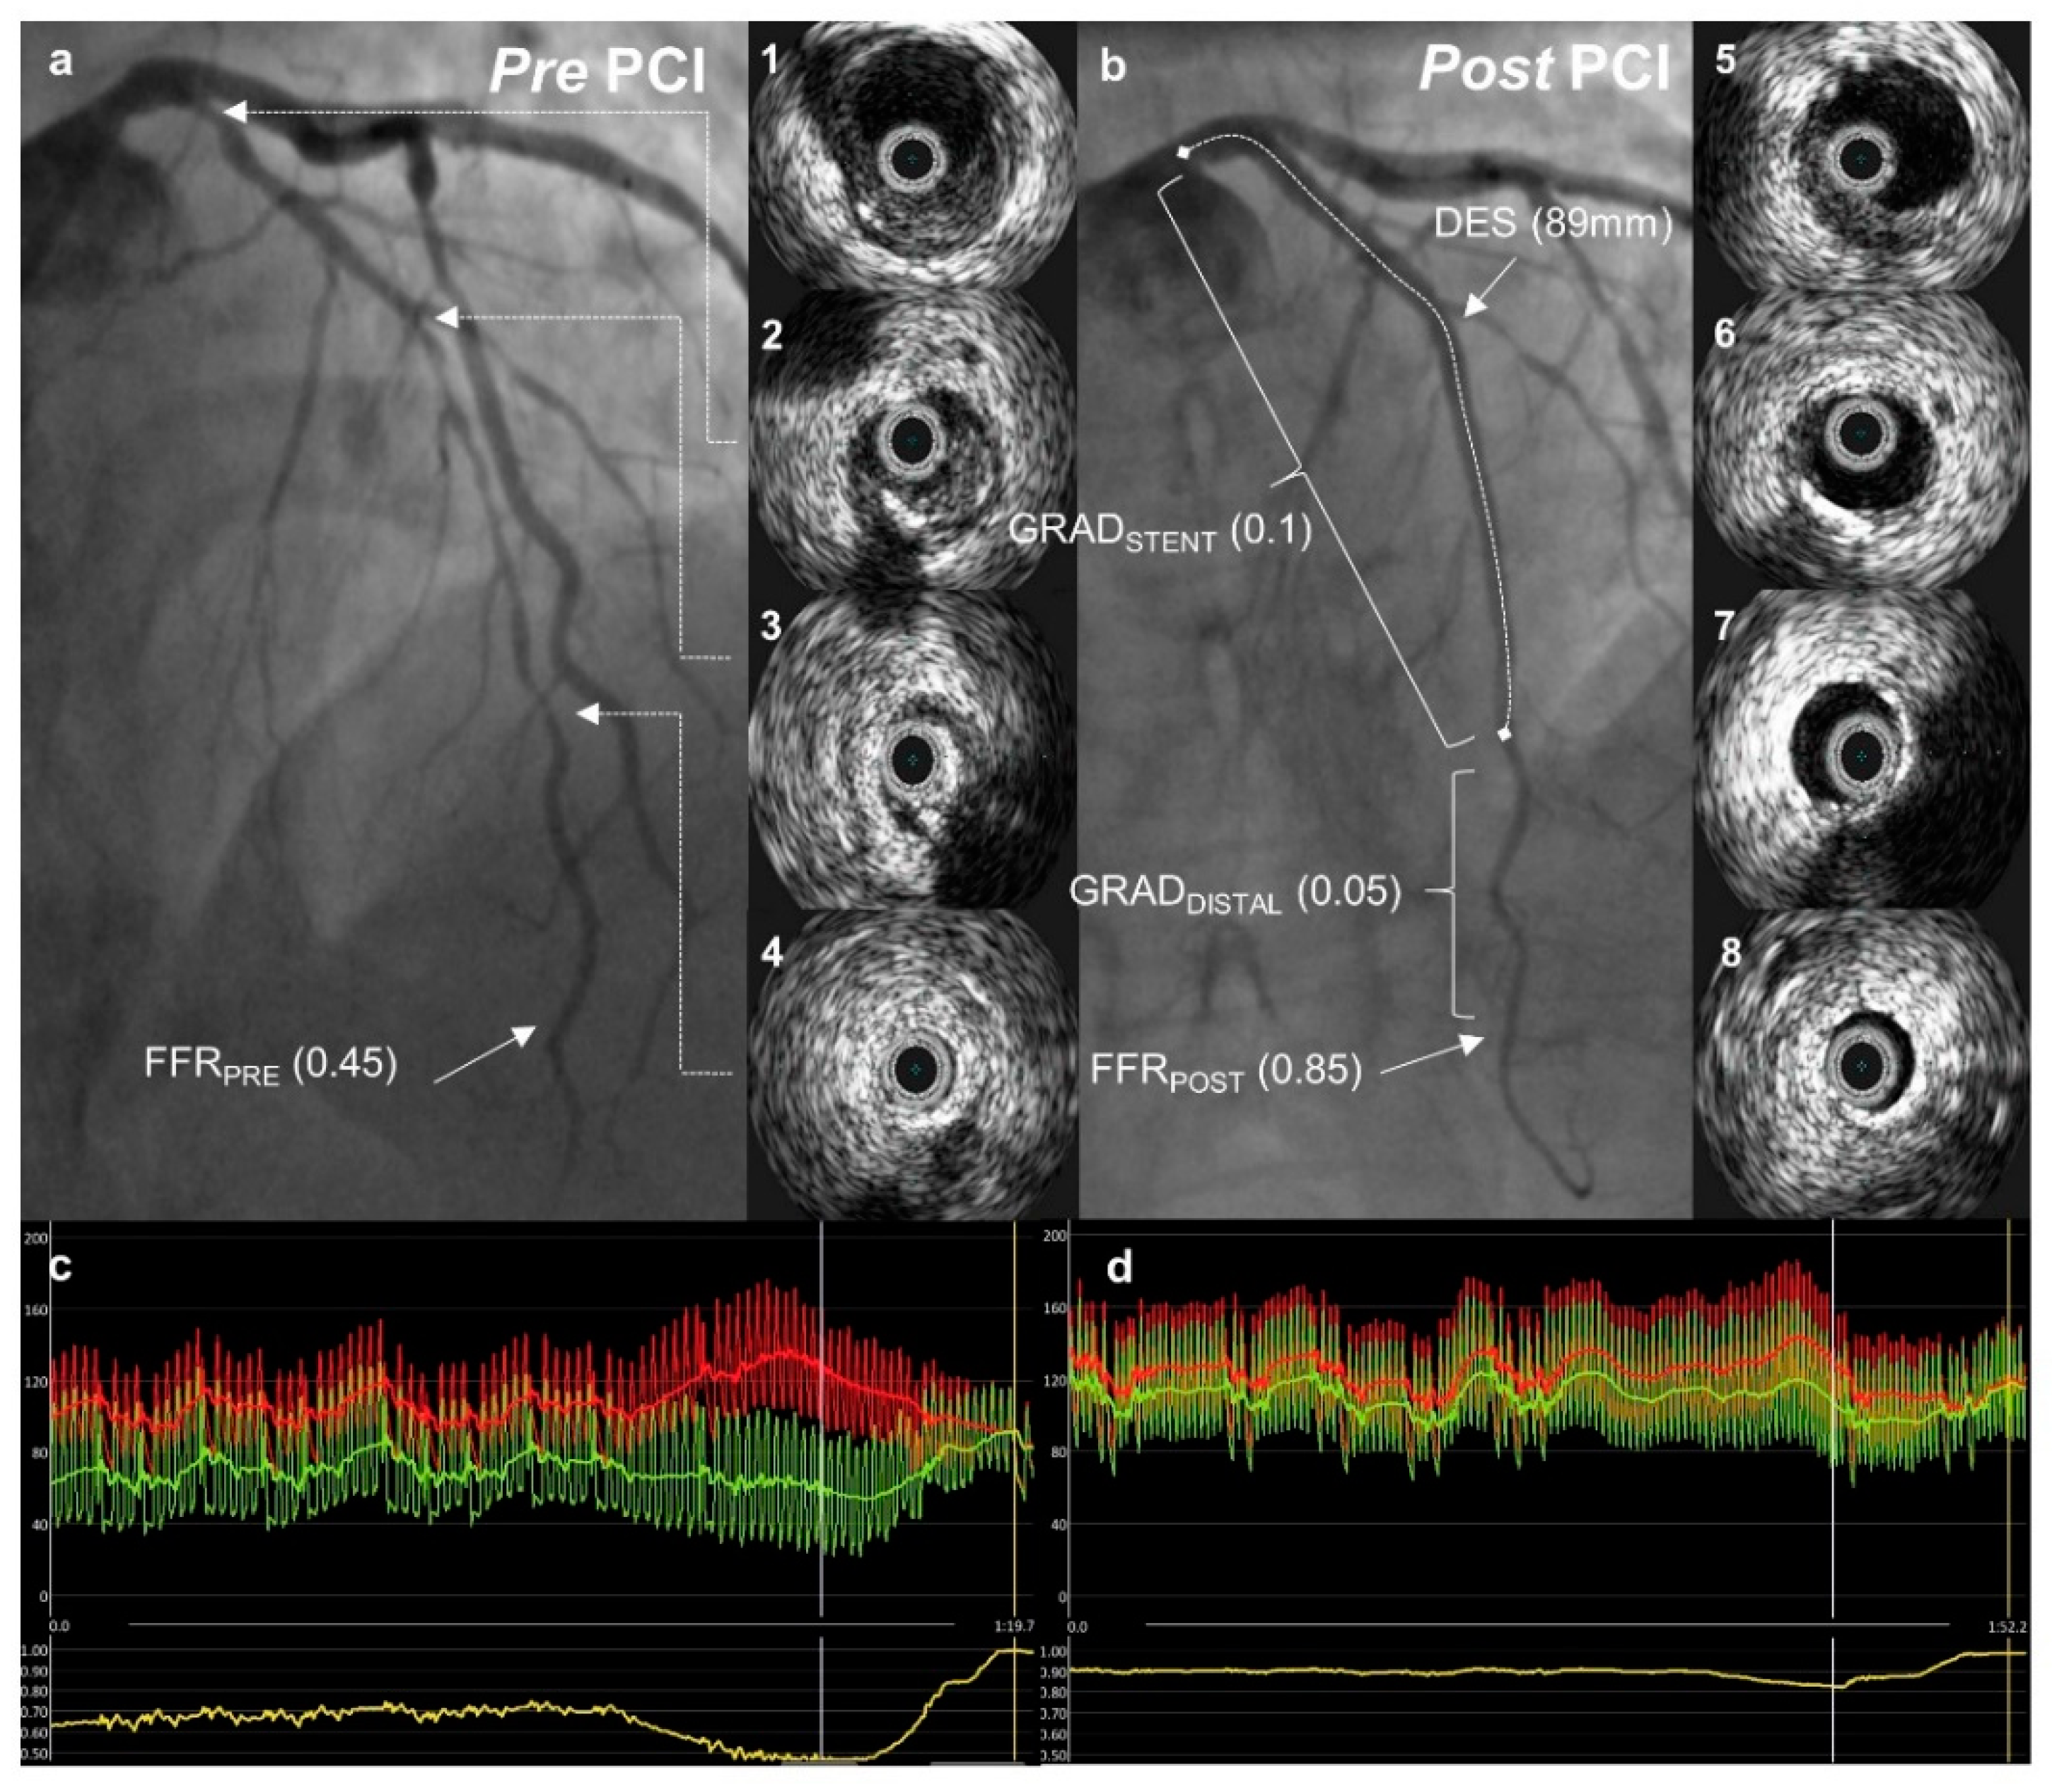

2.3. Fractional Flow Reserve Protocol

- FFRPOST—the FFR was measured in the same position as FFRPRE at the end of the PCI procedure after the final IVUS run.

- FFR gradient across the stent (GRADSTENT) was defined as the difference between the FFR value just proximal to the stent and the FFR value just distal to the stent.

- FFR gradient distal to the stent (GRADDISTAL) was defined as the difference between the FFR value just distal to the stent and the FFRPOST.